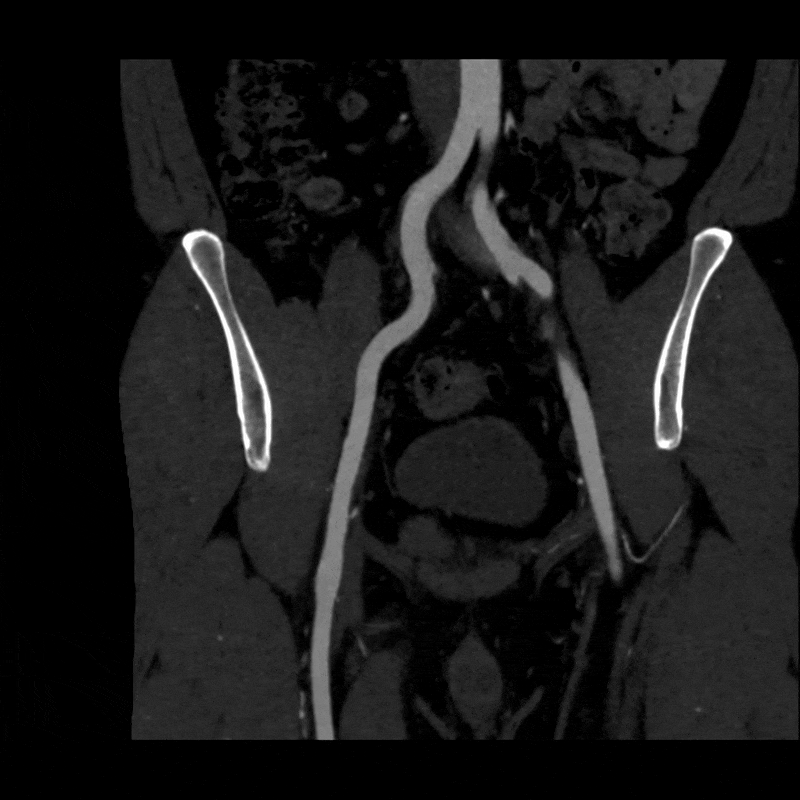

A dynamic CTA was performed in both relaxed and stressed (flexed) positions to simulate the limb posture during activity. Changes in hip and pelvic motion can alter the course of the external iliac artery, and narrowing that affects blood flow may appear only when the limb is under tension. Imaging at rest alone may overlook these positional changes, so evaluating both postures helps determine whether the symptoms are related to dynamic vessel deformation rather than fixed structural disease. (Learn about a similar condition, popliteal entrapment, here).

To better visualize the iliac anatomy, CPR loops were created to trace the artery along its course in both relaxed and stressed positions, allowing direct comparison of lumen size and curvature. VR views were generated with and without pelvic and femoral bone to show surrounding anatomical relationships. These complementary views help clarify how limb motion influences vessel shape and highlight narrowing that may be subtle or difficult to appreciate on axial slices alone. (Learn more about CPRs here, and VRs here).

When the patient moved into the stressed position, the right external iliac artery showed two areas of luminal narrowing (a temporary decrease in the size of the vessel’s opening). One narrowing was more proximal (closer to the vessel’s origin near the pelvis) at about ten to twenty percent, and the second was more distal (farther along the vessel toward the leg) at about thirty to forty percent. Both returned to a widely patent appearance (fully open) when the leg moved back to a relaxed position.

The left external iliac artery remained patent across positions, and the common iliac arteries were tortuous (naturally curving) without any fixed stenosis. This pattern aligns with external iliac endofibrosis, where motion causes the artery to change shape rather than a fixed obstruction, highlighting why positional imaging can reveal abnormalities that may not appear on routine resting studies.